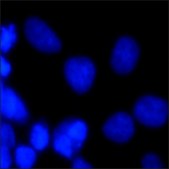

Application

Bisbenzimide Hoechst 33342 is a specific stain for AT-rich regions of double-stranded DNA and has been shown to displace several known DNA intercalators. This fluorescent dye has been used in sorting living cells based on DNA content, used in flow cytometry for the determination of DNA content, and for the visualization of chromatin distribution in living cells. It has been used to detect BrdU incorporation into cells and in studying the initial stages apoptosis and cellcycle distribution., Chromosomes that are dividing or replicating will not stain with this dye.

Useful for staining DNA, chromosomes and nuclei. May be used for fluorescence microscopy or flow cytometry.

Excitation max. = 346 nm

Emission max. = 460 nm